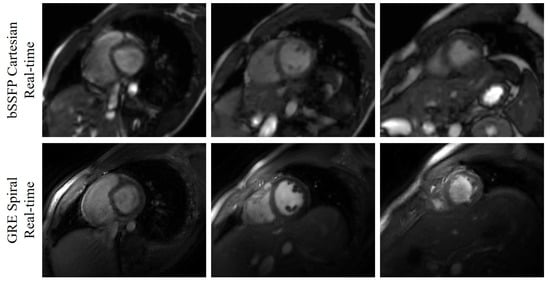

The output of each image has two channels, which correspond to the real and imaginary parts of the MR image. For the convolutional layers which have activation functions, we use Leaky ReLU with slope 0.2. Thirty-seven slices from five subjects were reconstructed in this work. Among the five subjects, we collected the basal slices for two subjects. The deep kernel method is also able to reconstruct the basal slices. The reconstructions of eight slices from Subject #2 were shown in Figure 2. We have also shown the comparison between the bSSFP Cartesian real-time images with acceleration factor 5 and the GRE spiral real-time images reconstructed using the deep kernel method in Figure 3.

Figure 3.

Comparison between the bSSFP Cartesian real-time images with acceleration factor 5 and the GRE spiral real-time images reconstructed using the deep kernel method. The three slices (one basal slice, one mid slice, and one apex slice) are from Subject #3. The first row shows the bSSFP Cartesian real-time images, and the second row is the GRE spiral real-time images.